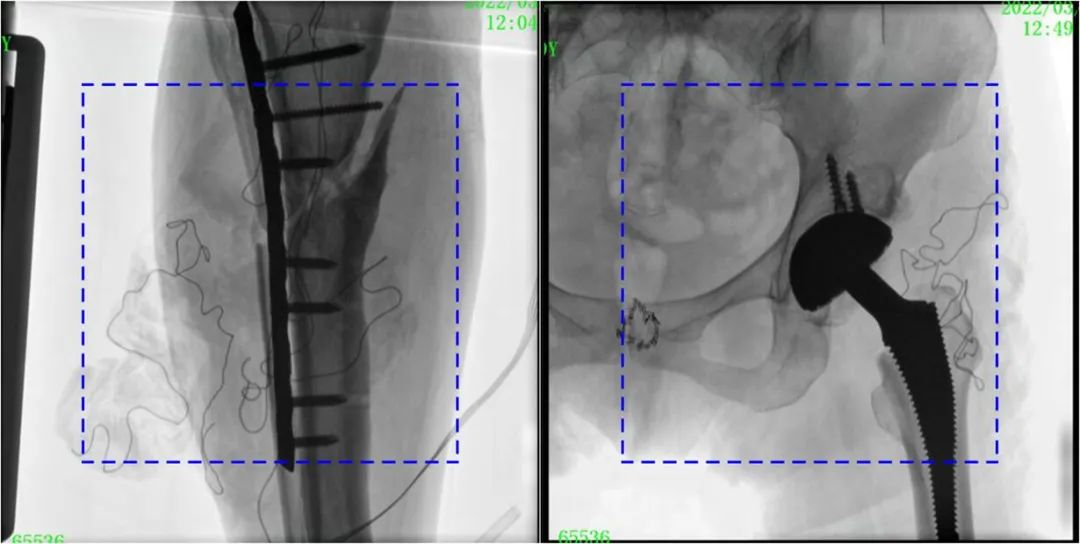

在進(jìn)行髓內(nèi)釘內(nèi)固定術(shù)時(shí),醫(yī)生需要同時(shí)觀察到入釘點(diǎn)和骨折部位的情況,普愛醫(yī)療大平板一體式C形臂采用30CM×30CM的平板探測(cè)器,能夠呈現(xiàn)更廣闊的成像面積,滿足大部分長(zhǎng)骨髓內(nèi)釘內(nèi)固定術(shù)的攝片需求。

PLX119C臨床圖像與傳統(tǒng)圖像對(duì)比

注:藍(lán)色虛線內(nèi)為傳統(tǒng)21CM×21CM平板的成像區(qū)域。